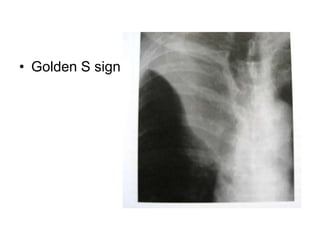

S Curve of Golden

• When there is a mass adjacent to a

fissure, the fissure takes the shape of an

"S". The proximal convexity is due to a

mass, and the distal concavity is due to

atelectasis.

Posteroanterior radiograph of the chest demonstrates the

Golden S sign. Note the convexity (arrowhead) from the

mass and the concavity (arrow) of the minor fissure

S Curve ofGolden • When there is a mass adjacent to a fissure, the fissure takes the shape of an "S". The proximal convexity is due to a mass, and the distal concavity is due to atelectasis.

Posteroanterior radiograph ofthe chest demonstrates the Golden S sign. Note the convexity (arrowhead) from the mass and the concavity (arrow) of the minor fissure